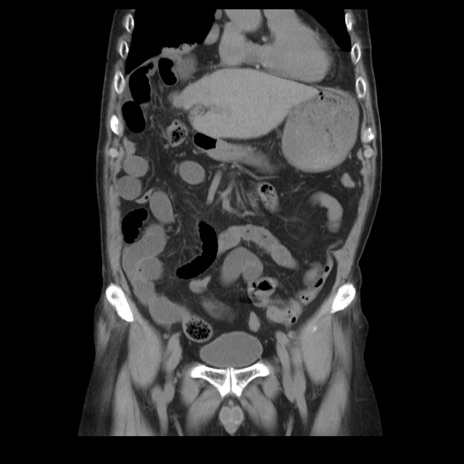

症例21(冠状断像)

【症例】70歳代男性

【主訴】腹痛

【現病歴】肝硬変・肝細胞癌にてかかりつけの方。約9時間前に食後より腹痛出現。症状が徐々に増悪し、嘔吐出現したため来院。

【既往歴】肝硬変、肝細胞癌(RFA、TACE後)

【身体所見】意識清明、表情苦悶様、BT 36℃、BP 129/78mmHg、P 88bpm、SpO2 97%(RA)、右上腹部から心窩部にかけて圧痛あり、反跳痛なし、筋性防御あり。

【データ】WBC 5800、CRP 0.16